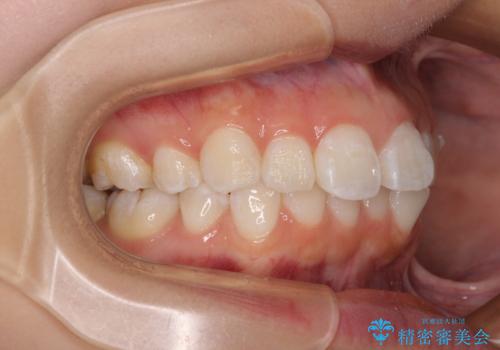

- 上下前歯の叢生を気にして来院された患者様です。

インビザラインでの治療を希望されていて、デコボコの程度が中等度であり、安価なパッケージにて対応可能と判断されたため、インビザライン・モデレートを用いて矯正治療を行うこととしました。